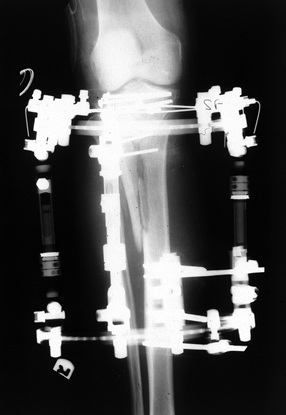

wire, or a combination of the two (hybrids). External fixators may be

placed across the fracture such that thin wires, with or without olive

beads, capture fracture fragments or across the knee joint in a

bridging fashion to make use of ligamentotaxis (38).

The key is placement of the pin or wire 10 to 14 mm below the articular

surface to avoid penetration of the synovial recess posteriorly. This

approach will help minimize the development of a septic joint from a

pin tract infection (46). Anatomic studies have

shown cadavers to have some communication between the tibial-fibular

joint and the knee joint. Thus a transfibular wire could potentially

seed the knee joint if a pin tract infection were to develop (46). Place smooth wires parallel to the articular surface and below any percutaneously placed screws (Fig. 23.15). If an Ilizarov construct is used, place half pins and wires into the intact tibial diaphysis below the fracture (13,16,38,57) (Fig. 23.16).

![]() |

|

Figure 23.16. The use of an Ilizarov external fixator to stabilize a Schatzker VI fracture.